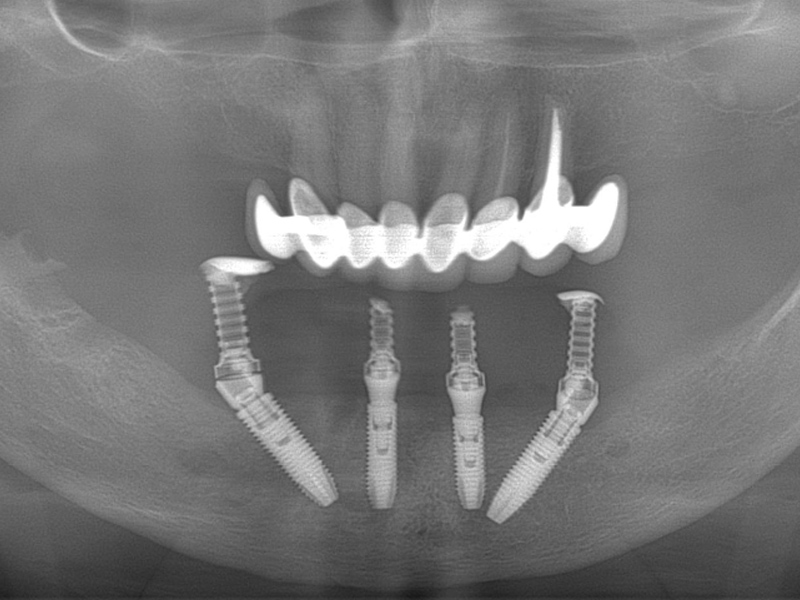

Using the All-On – 4 method; Dental implants are inserted in the same day and in a few hours, a temporary but fixed prosthetic job is performed immediately which will remain until the implants are perfectly integrated into the bone. After about 4-6 months, definitive prosthetic rehabilitation will be performed, which will be screwed onto existing implants. The screw fixing will allow you to remove the restoration (fixed bridge) when necessary.

The specificity of this procedure is that the teeth are fixed on four implants. Thanks to the particular method of inserting the implants, bone reconstruction is not necessary, which is instead a requirement when it is necessary to reconstruct in patients who have total tooth loss.

| absence of bone reconstruction |